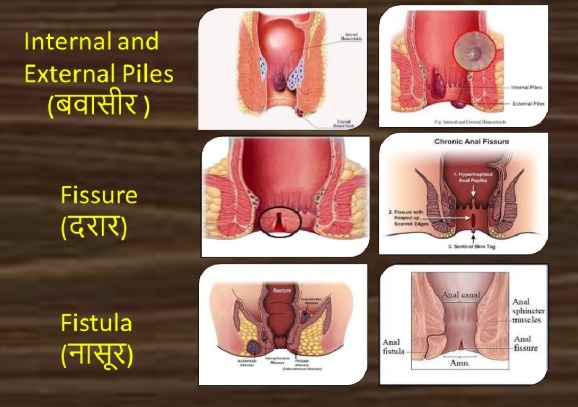

Digestive & Internal Care

We provide effective solutions for Piles, Fistula, Fissure, Chronic Constipation, and Gastric issues, alongside dedicated support for Liver and Kidney health.

Anorectal Care

Expert non-surgical treatment for Piles, Fistula, and Fissure. Get permanent relief from pain and discomfort naturally.

Piles / Fistula / Fissure

बवासीर / भगन्दर / फिशर